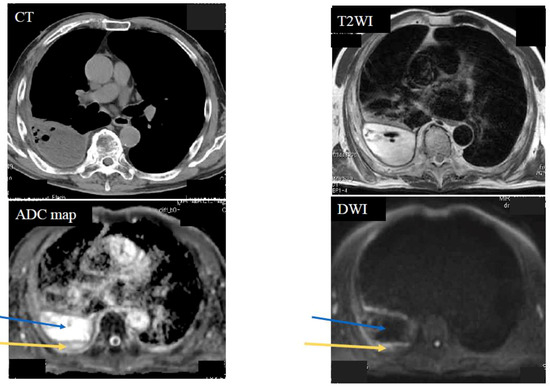

| Empyema | 0 | 0 | 10 | 0 | 10 | |